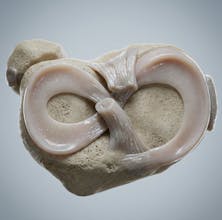

Natomy AI creates high-quality, medically accurate images and videos of human anatomy. Start with image-to-image: upload any low-quality photo, real image, or animation, and Natomy transforms it into an ultra-realistic anatomical visual. Unlike other AI tools that get anatomy wrong, Natomy is accurate every time—and fully editable by simply highlighting what you want changed and describing the update. Text-to-video launches in 2 weeks.